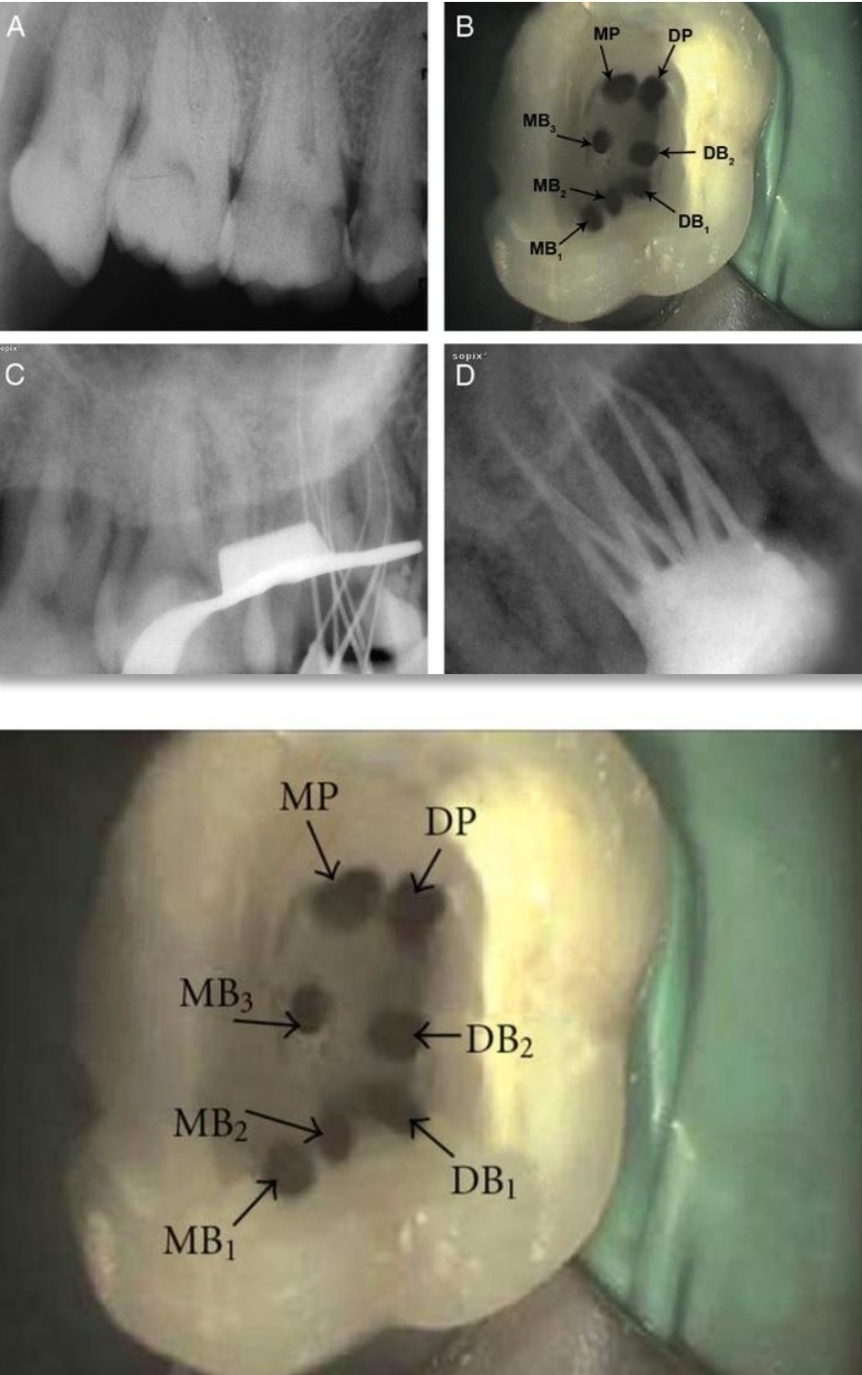

Anomalies of Maxillary first molar?

Single root and canal

2 distal canals

2 palatal roots

3 MB caals

8 canals